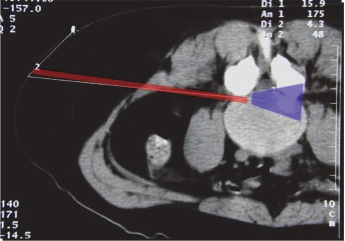

It is the “Kambin triangle” (the safe corridor to the lumbar disc between the exiting nerve root and the superior facet) which reminds us of his pioneering work (Figure 9).

這是“Kambin三角”(出口神經(jīng)根和上小關(guān)節(jié)之間可直入腰椎間盤的安全走廊),這讓我們想起他所做過的開創(chuàng)性工作(圖9)。

Figure 9: Kambin’s triangle for a safe posterolateral approach.

圖9:安全后外側(cè)入路的Kambin三角。